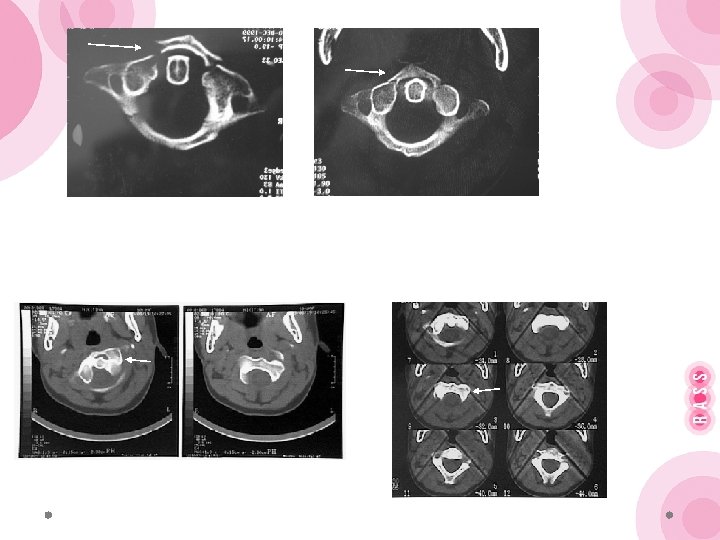

Гало-аппарат стал массово использоваться при переломах Джефферсона, переломах зубовидного отростка С 2, переломах «палача» , а также после стабилизирующих оперативных вмешательств, особенно когда выполняется обширная резекция позвонков (опухоли, инфекционные поражения, анкилозирующий спондилоартрит). Противопоказанием к наложению галоаппарата является нестабильные переломы костей черепа, повреждение кожных покровов головы в месте введения стержней.